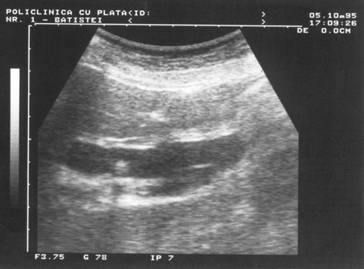

Figura 16. Intarire acustica posterioara la nivelul vezicii urinare.

Figura 17.}ntarire acustica posterioara la nivelul V.B.